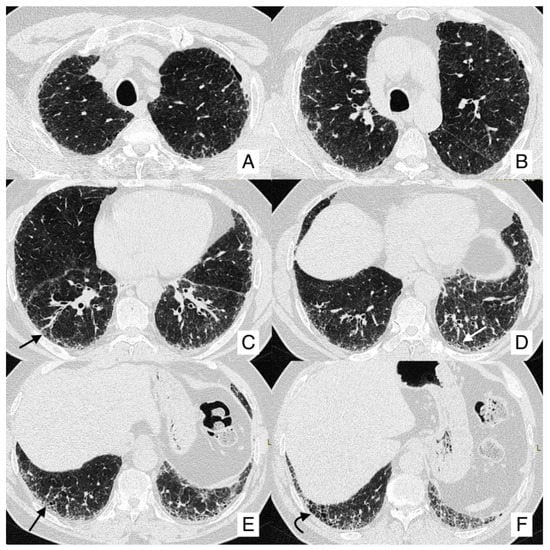

4.1. Lung Cancer